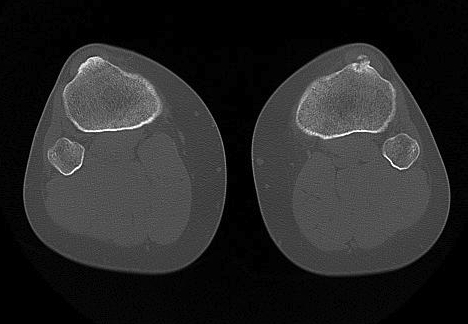

CT

1. Skyline View

Assess for

- lateral tilt

- subluxation

- trochlea dysplasia

2. Lateralisation of tibial tuberosity

Jones et al Skeletal Radiology

Superimpose 2 axial slices

A. Axial slice of trochlea

- line of posterior condyles

- line perpendicular through trochlea

B. Slice through tibial tuberosity

- perpendicular line through TT

Calculate Distance between two points / TTTG

10 - 15 mm normal, > 15 abnormal